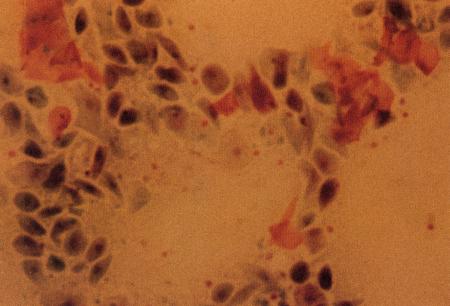

Фиг. 1.3.

Эндоскопическое исследование слизистой влагалища. Динамика изменений на протяжении цикла: (а) проэтрус — розовая окраска и отечность; (b) начало эструса — слизистая бледнеет, отек начинает уменьшаться (обычно перед пиком ЛГ); (c) середина эструса — слизистая бледная, уменьшение отека (сморщивание) явно выражено, что соответствует середине фертильного периода; (d) начало метэструса — видны закругленные складки, при прикосновении слизистая смыкается, образуя розетку (е) (см. Приложение)